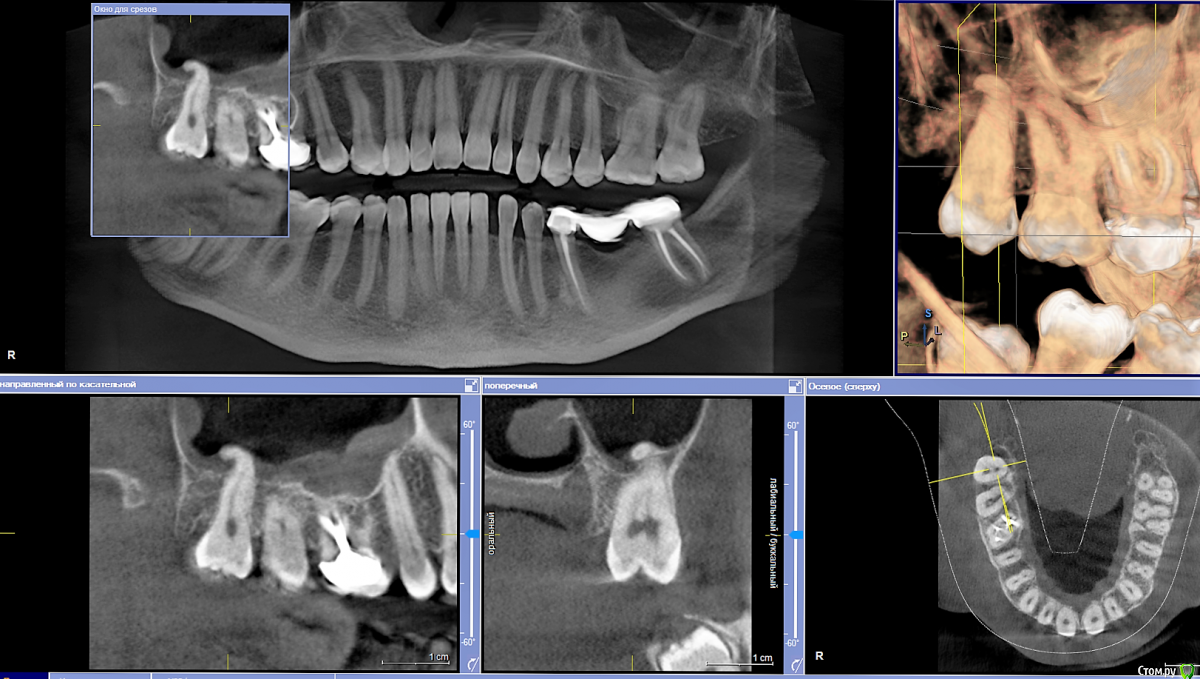

Ponchik Опубликовано 31 октября, 2015 Поделиться Опубликовано 31 октября, 2015 Удалить 18 без визита в синус и целиком не реально? Ссылка на комментарий

Ponchik Опубликовано 1 ноября, 2015 Автор Поделиться Опубликовано 1 ноября, 2015 какие показания для удаления? случайно увидел на КТ у терапевта, чувствую пришлють. Политика клиники все восьмерки на выход. страх апекс в пазухе оставить Думаю может сразу отправить тому, кто в синусе работать умеет. Ссылка на комментарий

Kev Опубликовано 1 ноября, 2015 Поделиться Опубликовано 1 ноября, 2015 Доктор, помните, что на КТ всегда все страшнее выглядит=))) верхние 8ки не повод для паники. Не торопясь расшатать щипчиками/элеватором и все прекрасно выйдет, главное не форсировать события, тем более вы знаете его анатомию. А от судьбы не уйдешь. Ну будет ОАС, так зашьете, тем более, что в области 8х все хорошо заживает, апекс сломаете - аккуратно достанете, методик много, все по ситуации. Главное, чтобы доктор был уверен в себе, это пациенты чувствуют очень хорошо. Ссылка на комментарий

Ponchik Опубликовано 1 ноября, 2015 Автор Поделиться Опубликовано 1 ноября, 2015 ОАС и правда не проблема. В пазуху забраться проблема. Не умею и это жутко напрягает. Просто в сентябре два случая было, когда подобные апексы отлетали в трифуркации седьмого и шестого. Отправлял в стационар. До этого несколько лет везло. То подхвачу каким зажимом, то пинцетом. Ссылка на комментарий

Rania Опубликовано 3 ноября, 2015 Поделиться Опубликовано 3 ноября, 2015 (изменено) на моей практике не попадались отломанные апексы которые я достал слюникомна моей тоже. Либо прямым элеватором, либо тоненькими щипцами. Если уж никак никак-оставляю, потом сам вылезет. Если так подумать чисто теоретически, если лунка такая большая, что туда слюноотсос дошел до апекса, то значит и щипцы есть куда наллжить. А вообще, если честно, с этими восьмерками иногда думаешь зачем вообще я рентген делала? Только в панику впадаешь после него.По снимку бывает корни в пазухах, загнутые в рогалик или нч нерв между корнями, а на деле все прекрасно удаляется легким движением элеватора. В данном случае перелома апекса быть не должно, он же в пазухе, а не в кости. Главное потом зашить. Изменено 3 ноября, 2015 пользователем Rania Ссылка на комментарий

Ponchik Опубликовано 3 ноября, 2015 Автор Поделиться Опубликовано 3 ноября, 2015 (изменено) Через средний носовой ход ))) Апекс имеет изгиб дистально и последние мм идут уже коронально. Тут выход в декапитации зуба и вывихивание зуба в дистальном направлении. Но теперь это история. Пациентка прониклась возможными осложнениями и не решилась на удаление.Всегда пугаю основательно, что бы так не вышло - http://forum.stom.ru/topic/30857-udaleniia-zuba-mudrosti/Хотя один раз было, когда пациентку пугал-пугал(полчаса), но не впечатлил и удаление 38 зуба произошло. А через два дня потом говорила, что ничего не было, ни о чем её не предупреждали(была парастезия альвеолярного). С транспарантами и группой поддержки поход к заведующему и главврачу. А там... видео Лица сутяжников видеть надо было. С тех пор камеры в кабинетах уважаю. Только в носу ковыряться неловко, вдруг непоймутс. Изменено 3 ноября, 2015 пользователем Ponchik Ссылка на комментарий